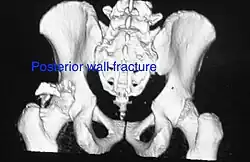

Posterior wall fracture as seen on 3-D CT scan -